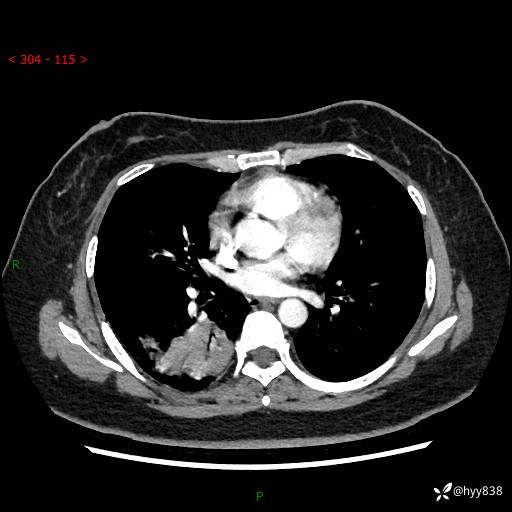

胸部CT平扫